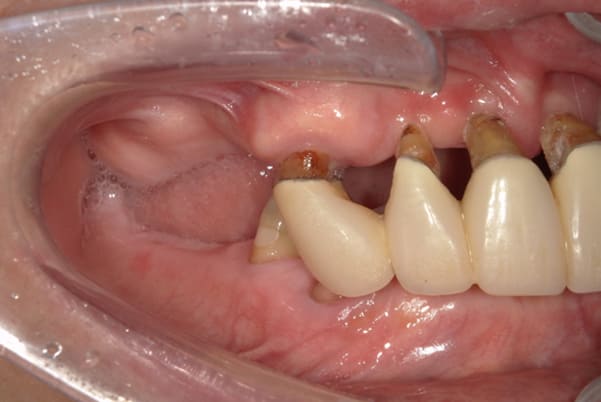

入れ歯が沈み込むことを防止するストッパーがない入れ歯を装着されていたため、お食事により入れ歯が沈み込みお痛みがでている状態でした。

笑った際に、太いバネが左右に見えるため、あまり大きく笑うことを避けていらっしゃいました。

こちらは、口を少し開いた時の治療前と治療後の

口元です。

正面から見た時にクラスプが目立たないように、

歯ぐきになじむ素材にて入れ歯を製作し、痛くなく自然に馴染み快適に生活を送れるようになりました。